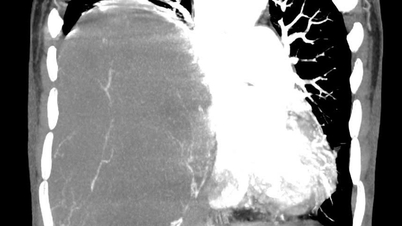

Phim chụp CT ổ bụng của bệnh nhân.

Chẩn đoán hình ảnh (CT ổ bụng có thuốc cản quang) cho thấy khối choán chỗ sau phúc mạc, kích thước 28 × 15 cm, cấu trúc hỗn hợp tổ chức mỡ – đặc , đè đẩy tạng trong ổ bụng nhưng không có dấu hiệu xâm lấn các tạng lân cận. Kết hợp lâm sàng và hình ảnh học, bệnh nhân được chẩn đoán sarcoma mỡ sau phúc mạc.